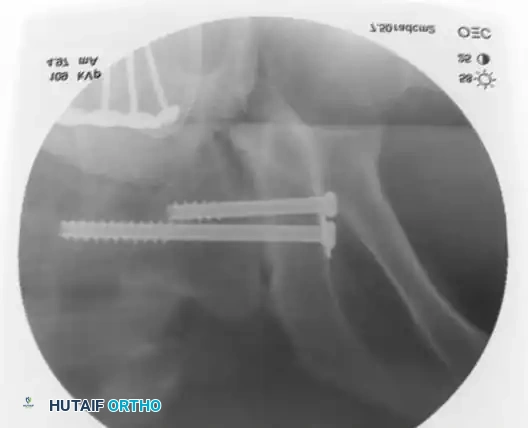

3. Percutaneous Sacroiliac (SI) Screws (Posterior Ring)

The gold standard for posterior ring fixation in appropriately selected patients.

* Indications: Sacral fractures, SI joint disruptions, crescent fractures.

* Technique: Performed under strict fluoroscopic guidance (Inlet, Outlet, and Lateral sacral views).

* Trajectory: The guide wire is advanced from the lateral ilium, across the SI joint, into the S1 (or S2) vertebral body.

* Safety Corridors: The surgeon must possess an intimate understanding of sacral dysmorphism. The "safe zone" is bounded by the sacral neural foramina inferiorly, the spinal canal posteriorly, and the sacral ala anteriorly.

Pitfall: Failure to recognize a dysmorphic sacrum (characterized by upper sacral segment elevation, non-recessed alae, and oblique neural foramina) can lead to catastrophic L5 nerve root injury or vascular penetration during SI screw placement.